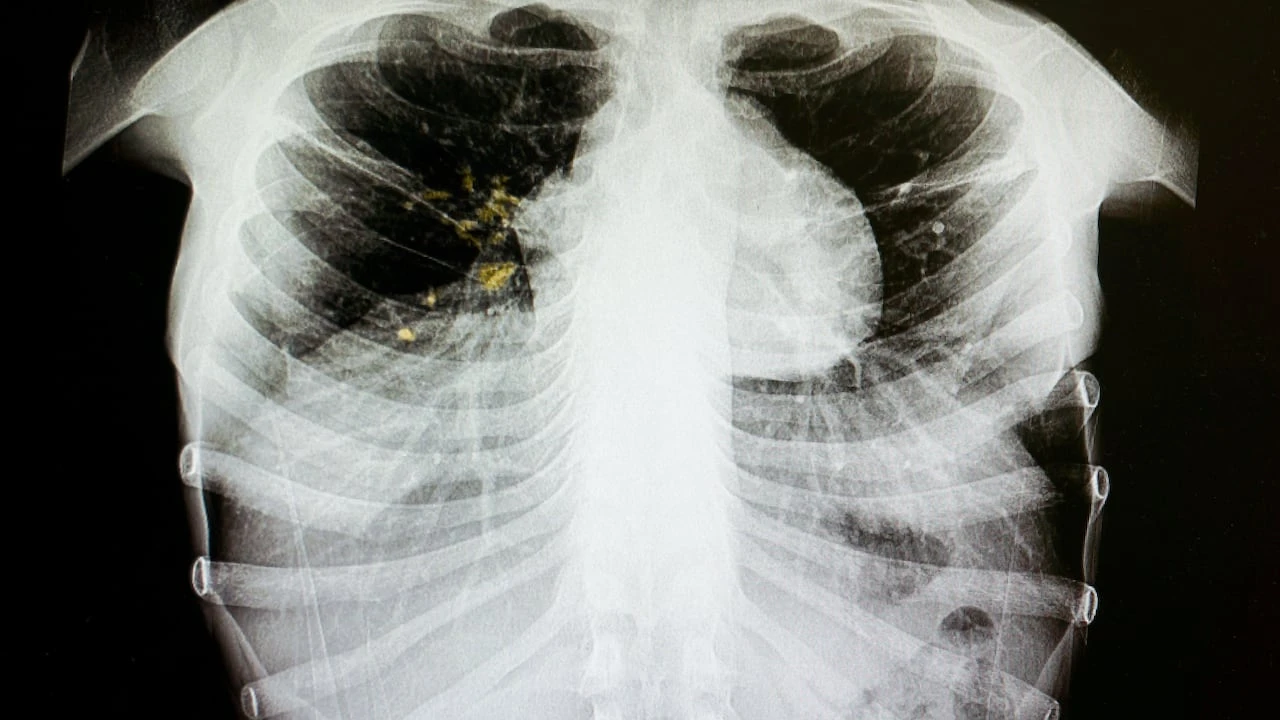

Tuberculosis outbreak declared in inner-city Edmonton: Primary Care Alberta